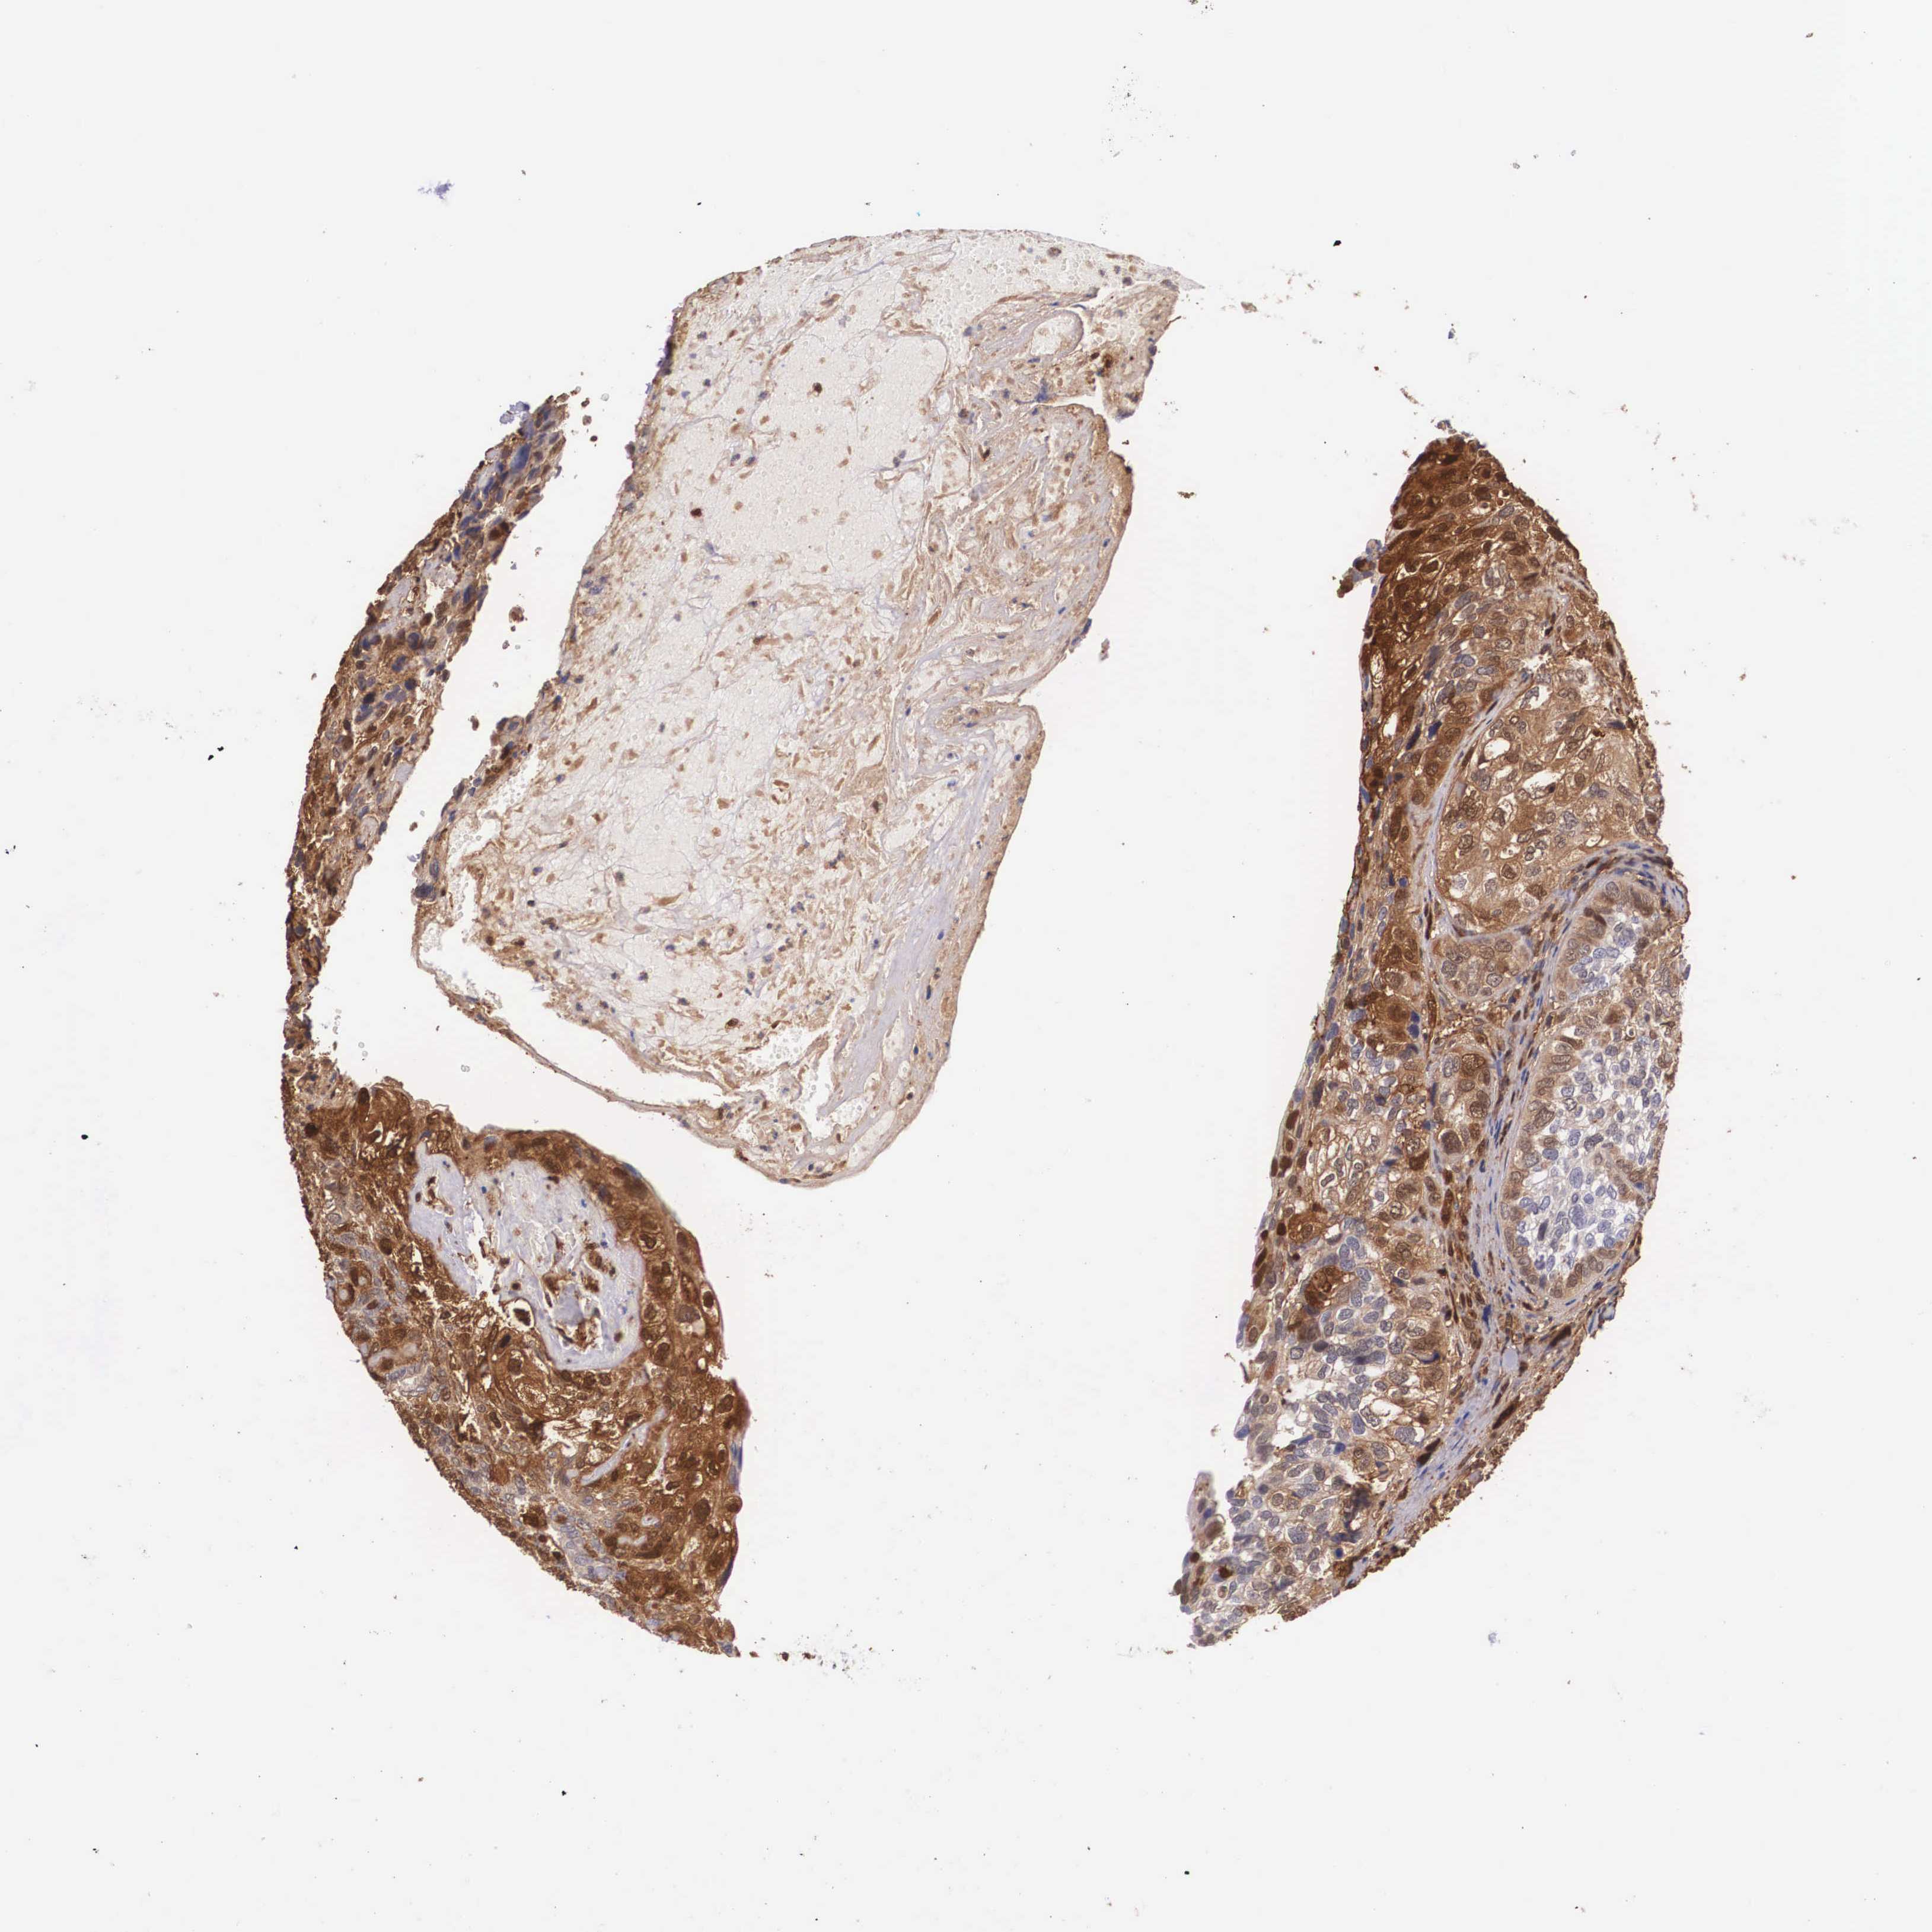

BRCA TCGA BRCA VALIDATION PROTEIN EXPRESSION

ANTIBODIES

AND

VALIDATION